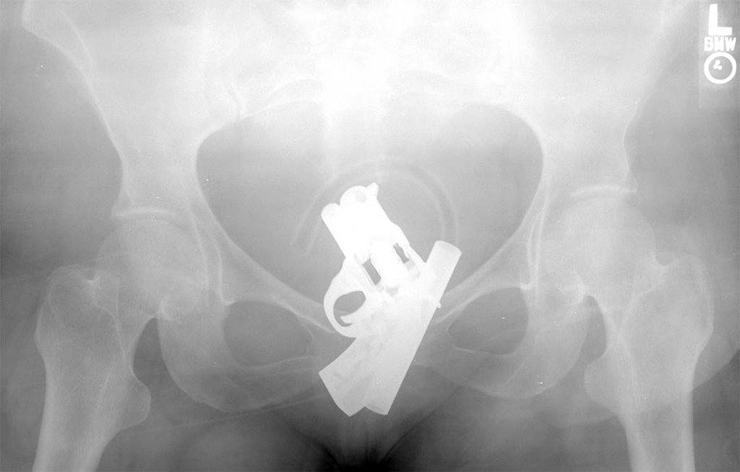

Пистолет

Сами видите, где находится пистолет.